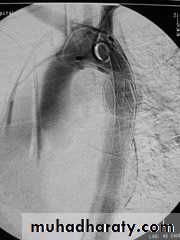

• 6-Great vessels injuriesInjuries to the thoracic aorta and its branches can occur mainly with deceleration injury . Most patients with ruptured aorta die immediately but in 10% of patients the per aortic tissues and pleura are able to maintain the intravascular pressure producing false aneurysms ,which can be diagnose by CT angiography and needs immediate surgery .

Traumatic aortic disruption is a time-sensitive injury requiring rapid and accurate diagnosis to prevent death.

Descending aortic injuryEndo vascular stent control